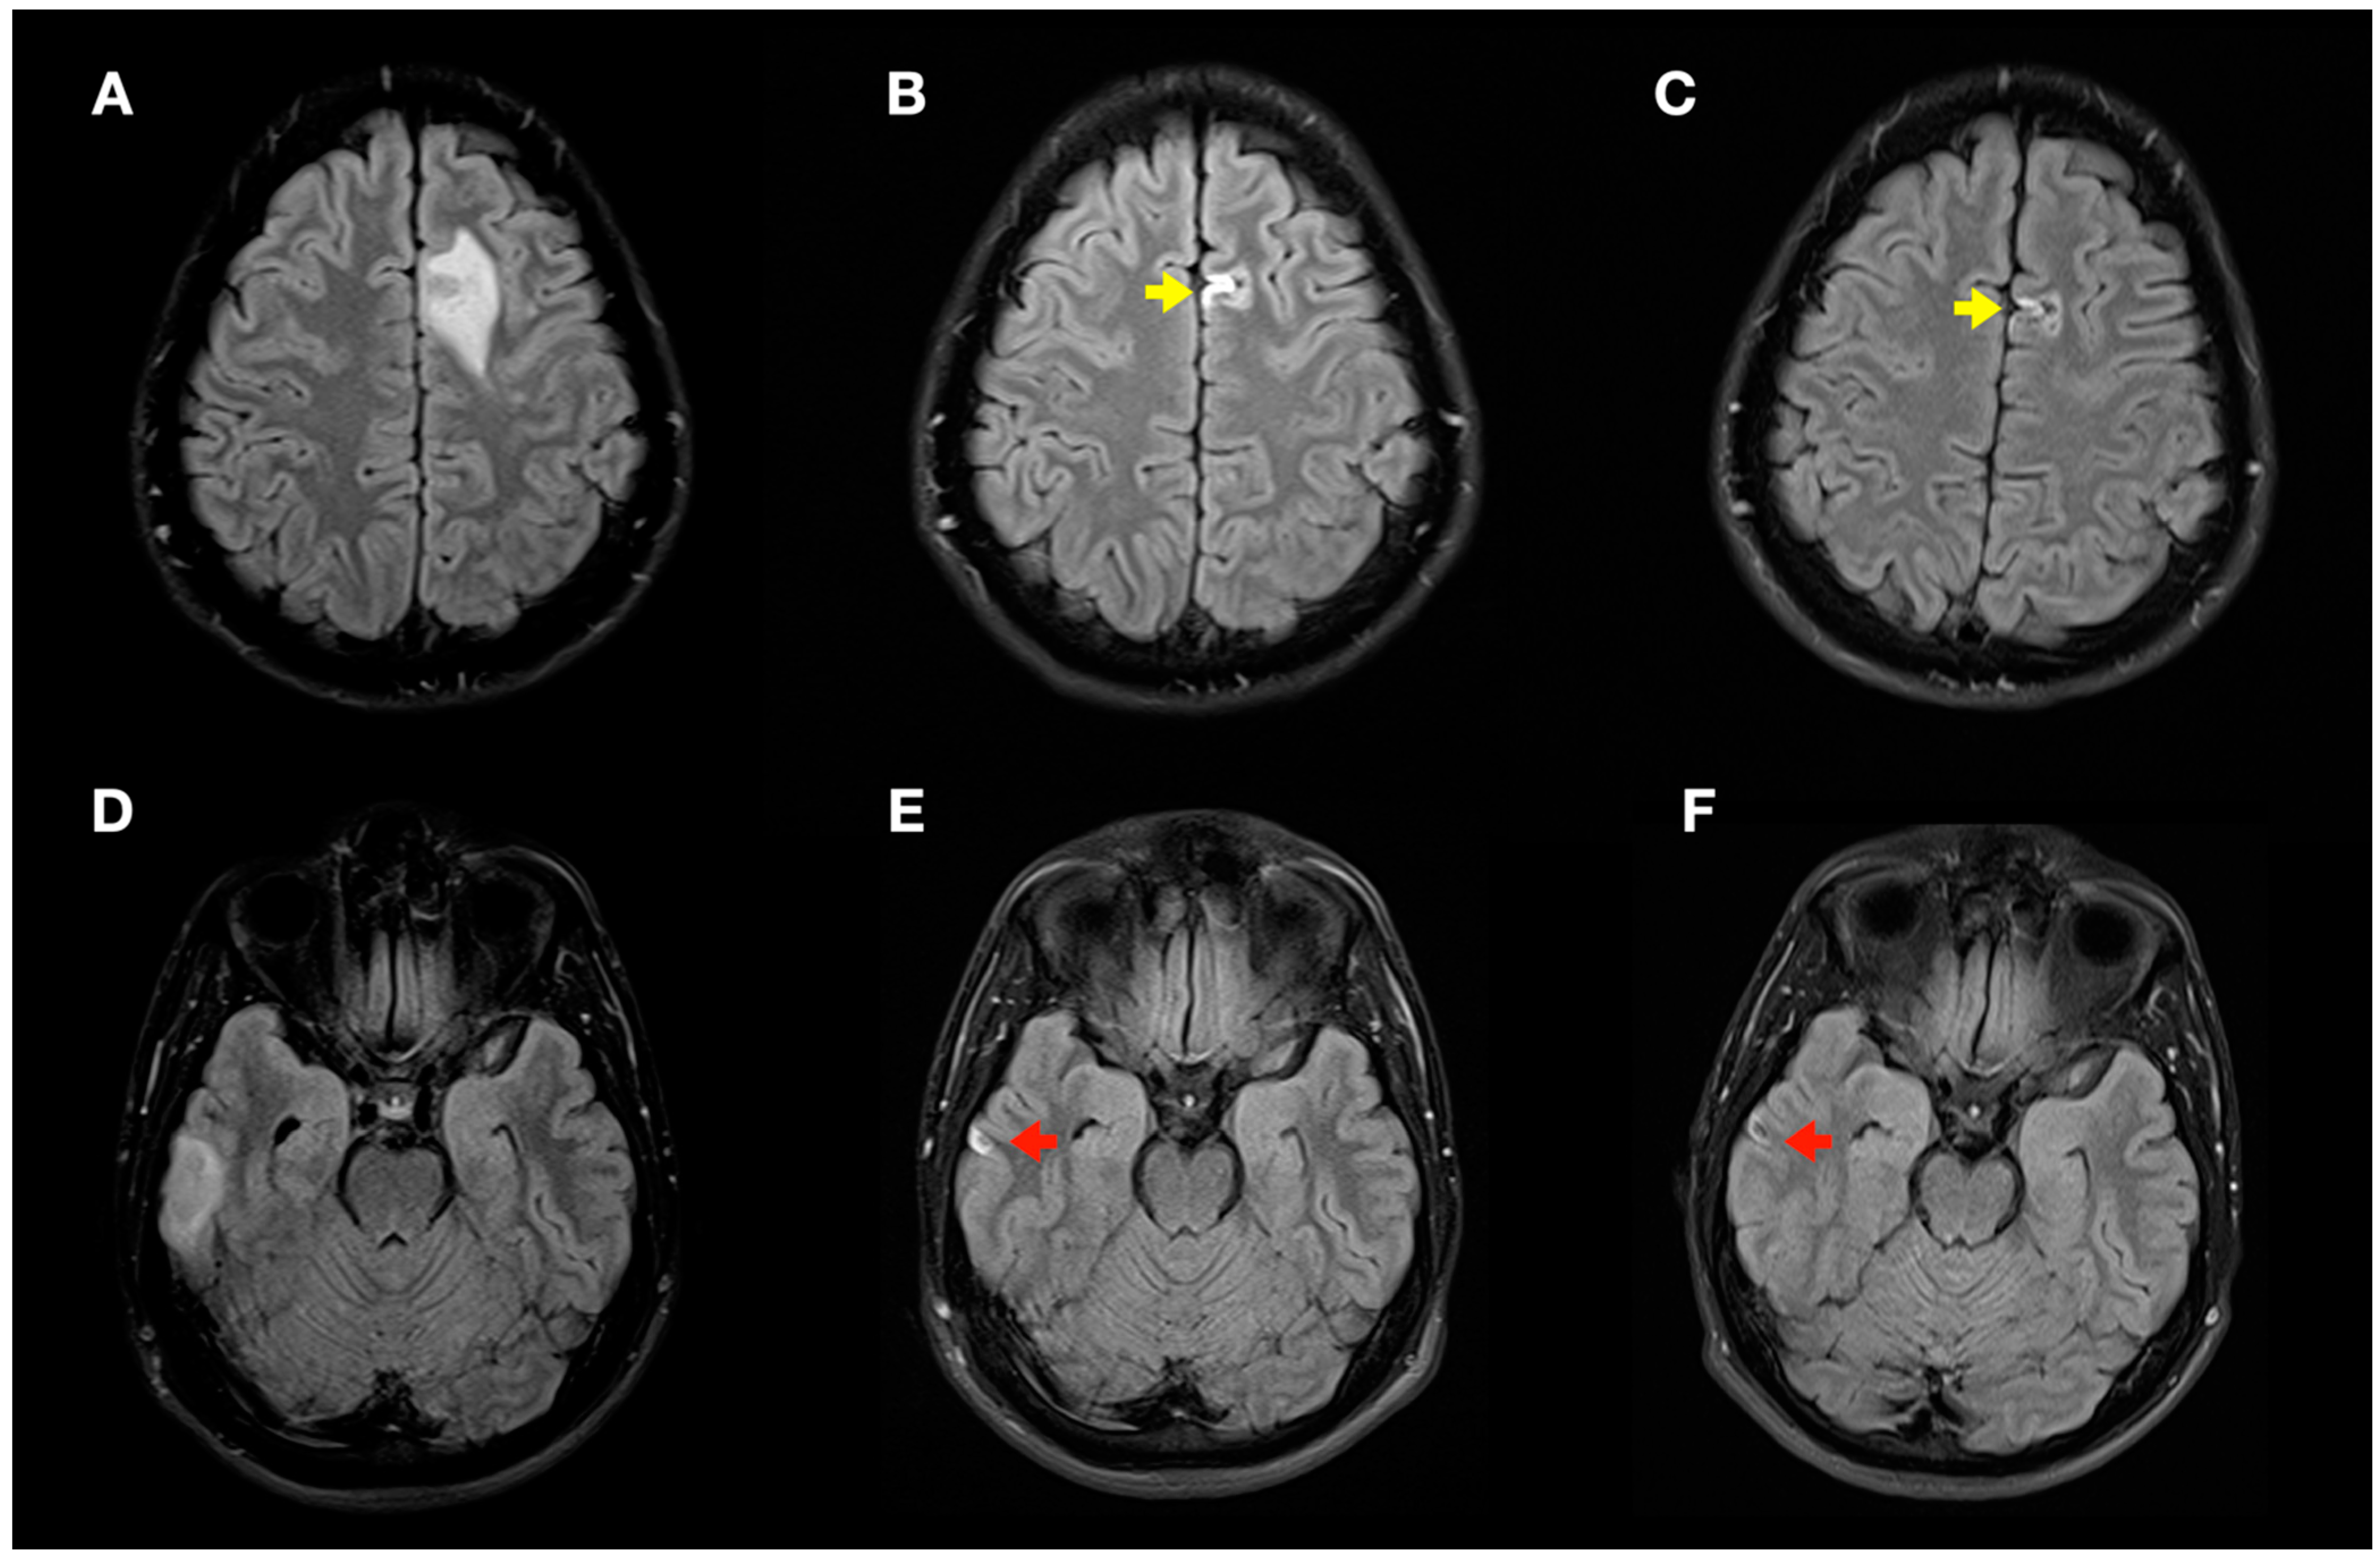

Figure 6.

Radiological evolution of lesions secondary to decompression sickness: axial FLAIR images. (A,D) Initial images: left frontal cortico-subcortical hyperintense lesion (A) and right temporal cortico-subcortical hyperintense lesion (D). (B,E) Image control at 1 month: minimal hyperintense lesions in the right temporal (red arrow) and left frontal (yellow arrow) lobes of the brain. (C,F) Image control at 4 months: minimal chronic lesions compatible with cerebral malacia in the right temporal (red arrow) and left frontal (yellow arrow) lobes of the brain.

During follow-up, the patient did not present any new neurological symptoms, and radiological improvement was observed in successive neuroimaging tests (Figure 6), with only minimal chronic cortical lesions compatible with areas of cerebral malacia in the right temporal and left frontal lobes of the brain.

Finally, in our case, control MRI (1 and 4 months after DCS) demonstrated resolution of the hyperintense bihemispheric vasogenic edema lesions on T2WI/FLAIR sequences and the ADC map, with only minimal areas of cerebral malacia persisting.